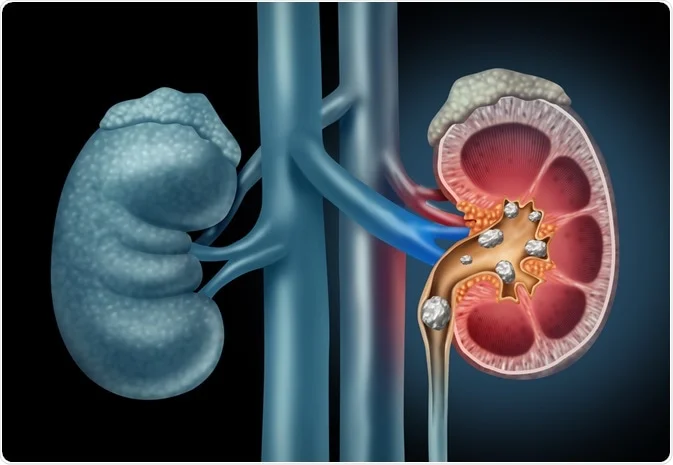

કિડની રોગ

કિડની સ્ટોન

ઘરગથ્થુ ઉપચારથી બચાવો કિડની

સવારે 1 ચમચી લીમડાના પાનનો રસ પીવો.

પીપળાના પાનનો રસ 1 ચમચી સાંજે પીવો.

કિડની રહેશે સ્વસ્થ

ગોખરુને પાણીમાં ઉકાળીને ઠંડુ કરો.

દિવસમાં બે વાર ગોખરુ પાણી પીવો

કિડની પત્થરો અને ચેપ અટકાવશે.

કિડનીની પથરી માટે ફાયદાકારક વસ્તુઓ

ખાટી છાશ

ઘોડા ગ્રામ કઠોળ

મૂળો

સ્ટોનક્રોપના પાંદડા

જવનો લોટ

કિડની પત્થરો માટે રામબાણ સારવાર

મકાઈના કોબ્સને પાણીમાં ઉકાળો

ફિલ્ટર કરો અને પીવો

કિડનીની પથરી દૂર કરે છે

UTI ચેપ દૂર થશે